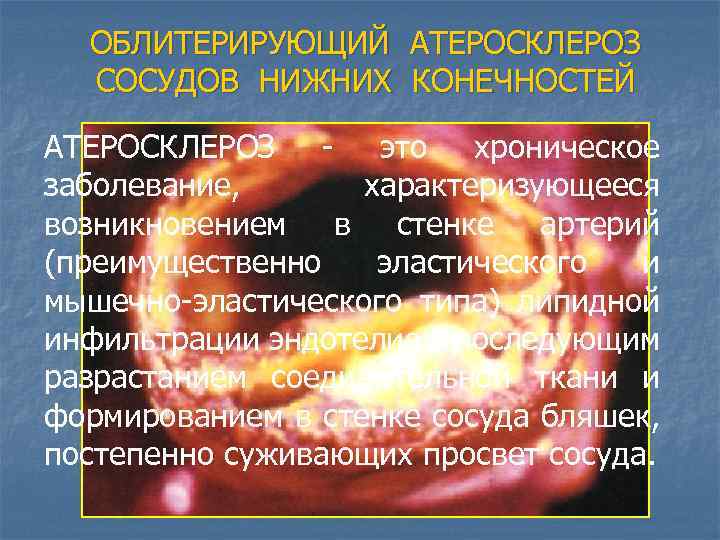

ОБЛИТЕРИРУЮЩИЙ АТЕРОСКЛЕРОЗ СОСУДОВ НИЖНИХ КОНЕЧНОСТЕЙ АТЕРОСКЛЕРОЗ - это хроническое заболевание, характеризующееся возникновением в стенке артерий (преимущественно эластического и мышечно-эластического типа) липидной инфильтрации эндотелия с последующим разрастанием соединительной ткани и формированием в стенке сосуда бляшек, постепенно суживающих просвет сосуда.